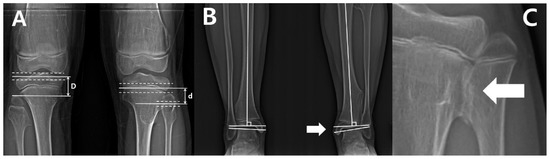

Figure 4. The serial radiographs of a male patient demonstrated progression of valgus deformity on the left ankle. Despite exostoses in bilateral legs, valgus angulation of the left ankle accompanied by shortening of the fibula was observed, while the neutral alignment was maintained on the right ankle. In the last measurement, the left tibial length was also about 9 mm shorter than the right tibia.